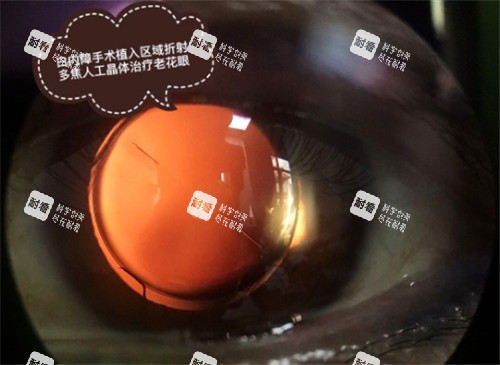

审核通过后,医院会联系患者确定手术时间(一般1-2周内就能排上)。手术用的是小切口超声乳化+人工晶体植入(现在主流术式,创伤小、改善快),全程大概10-15分钟,术后第二天就能拆纱布。